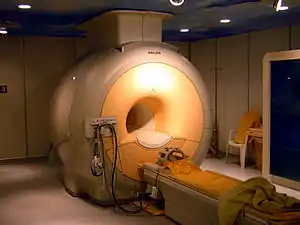

| Magnetic resonance imaging (MRI) alias Nuclear magnetic resonance (NMR) | high strength (0.15 to 1.5 teslas)[4] are used to excite protons that produce the record results (like CT scan). It can show particular tissues more clearly than CT.;[4] video link |

A 3 tesla MRI scanner

A 3 tesla MRI scanner fMRI scanner